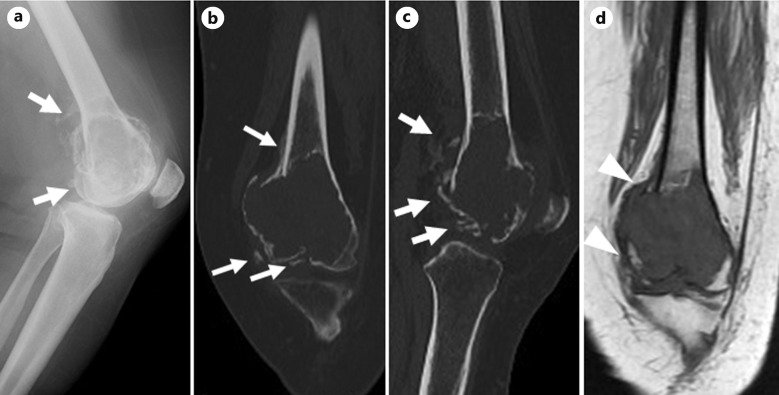

Case presentation: A 45-year-old woman with a pathological fracture of the left distal femur was diagnosed with GCTB based on the biopsy findings, which revealed both H3.3 G34W and nuclear β-catenin positivity. Eight courses of neoadjuvant denosumab therapy were administered to visualize the extraskeletal lesions; subsequently, en bloc resection with megaprosthetic reconstruction was successfully performed. Pathological examination revealed intratumoral ossification without osteoclastic giant cells. Two years after the surgery, no evidence of local recurrence was recorded.